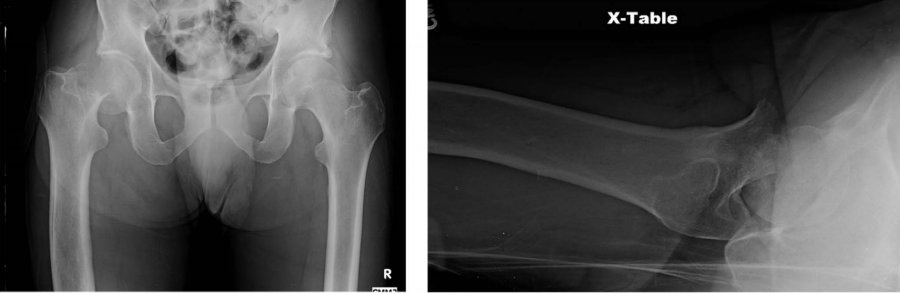

病例1:65岁的男性,不小心从台阶上摔下致右髋受伤。

病史:高血压、高胆固醇和既往吸烟史(30包年)。

患者现已退休,曾担任会计师,并且周末几乎每天都在社区的湖泊周围进行1到2英里的步行和10英里的自行车骑行。

他注意到受伤前偶尔会出现运动时腹股沟区疼痛。

研究人员对556名外科医生完成了在线调查,共有该调查包括两个部分:(1)外科医生的人口统计学信息;(2)要求对两个老年髋部骨折病例给出治疗决策。病例如上图所示。对股骨颈骨折的治疗考量和方案进行电子问卷调查,发出731份,收回有效问卷556份;其中390份医生经历关节外科训练、50份经历创伤骨科训练,该比例接近美国注册的比例(3156:619)。研究人员希望通过此研究对创伤骨科和关节外科医生进行调查,比较不同亚专业组间的培训及处理老年股骨颈骨折的差异,并将治疗方法与美国骨科医师学会临床实践指南进行比较。